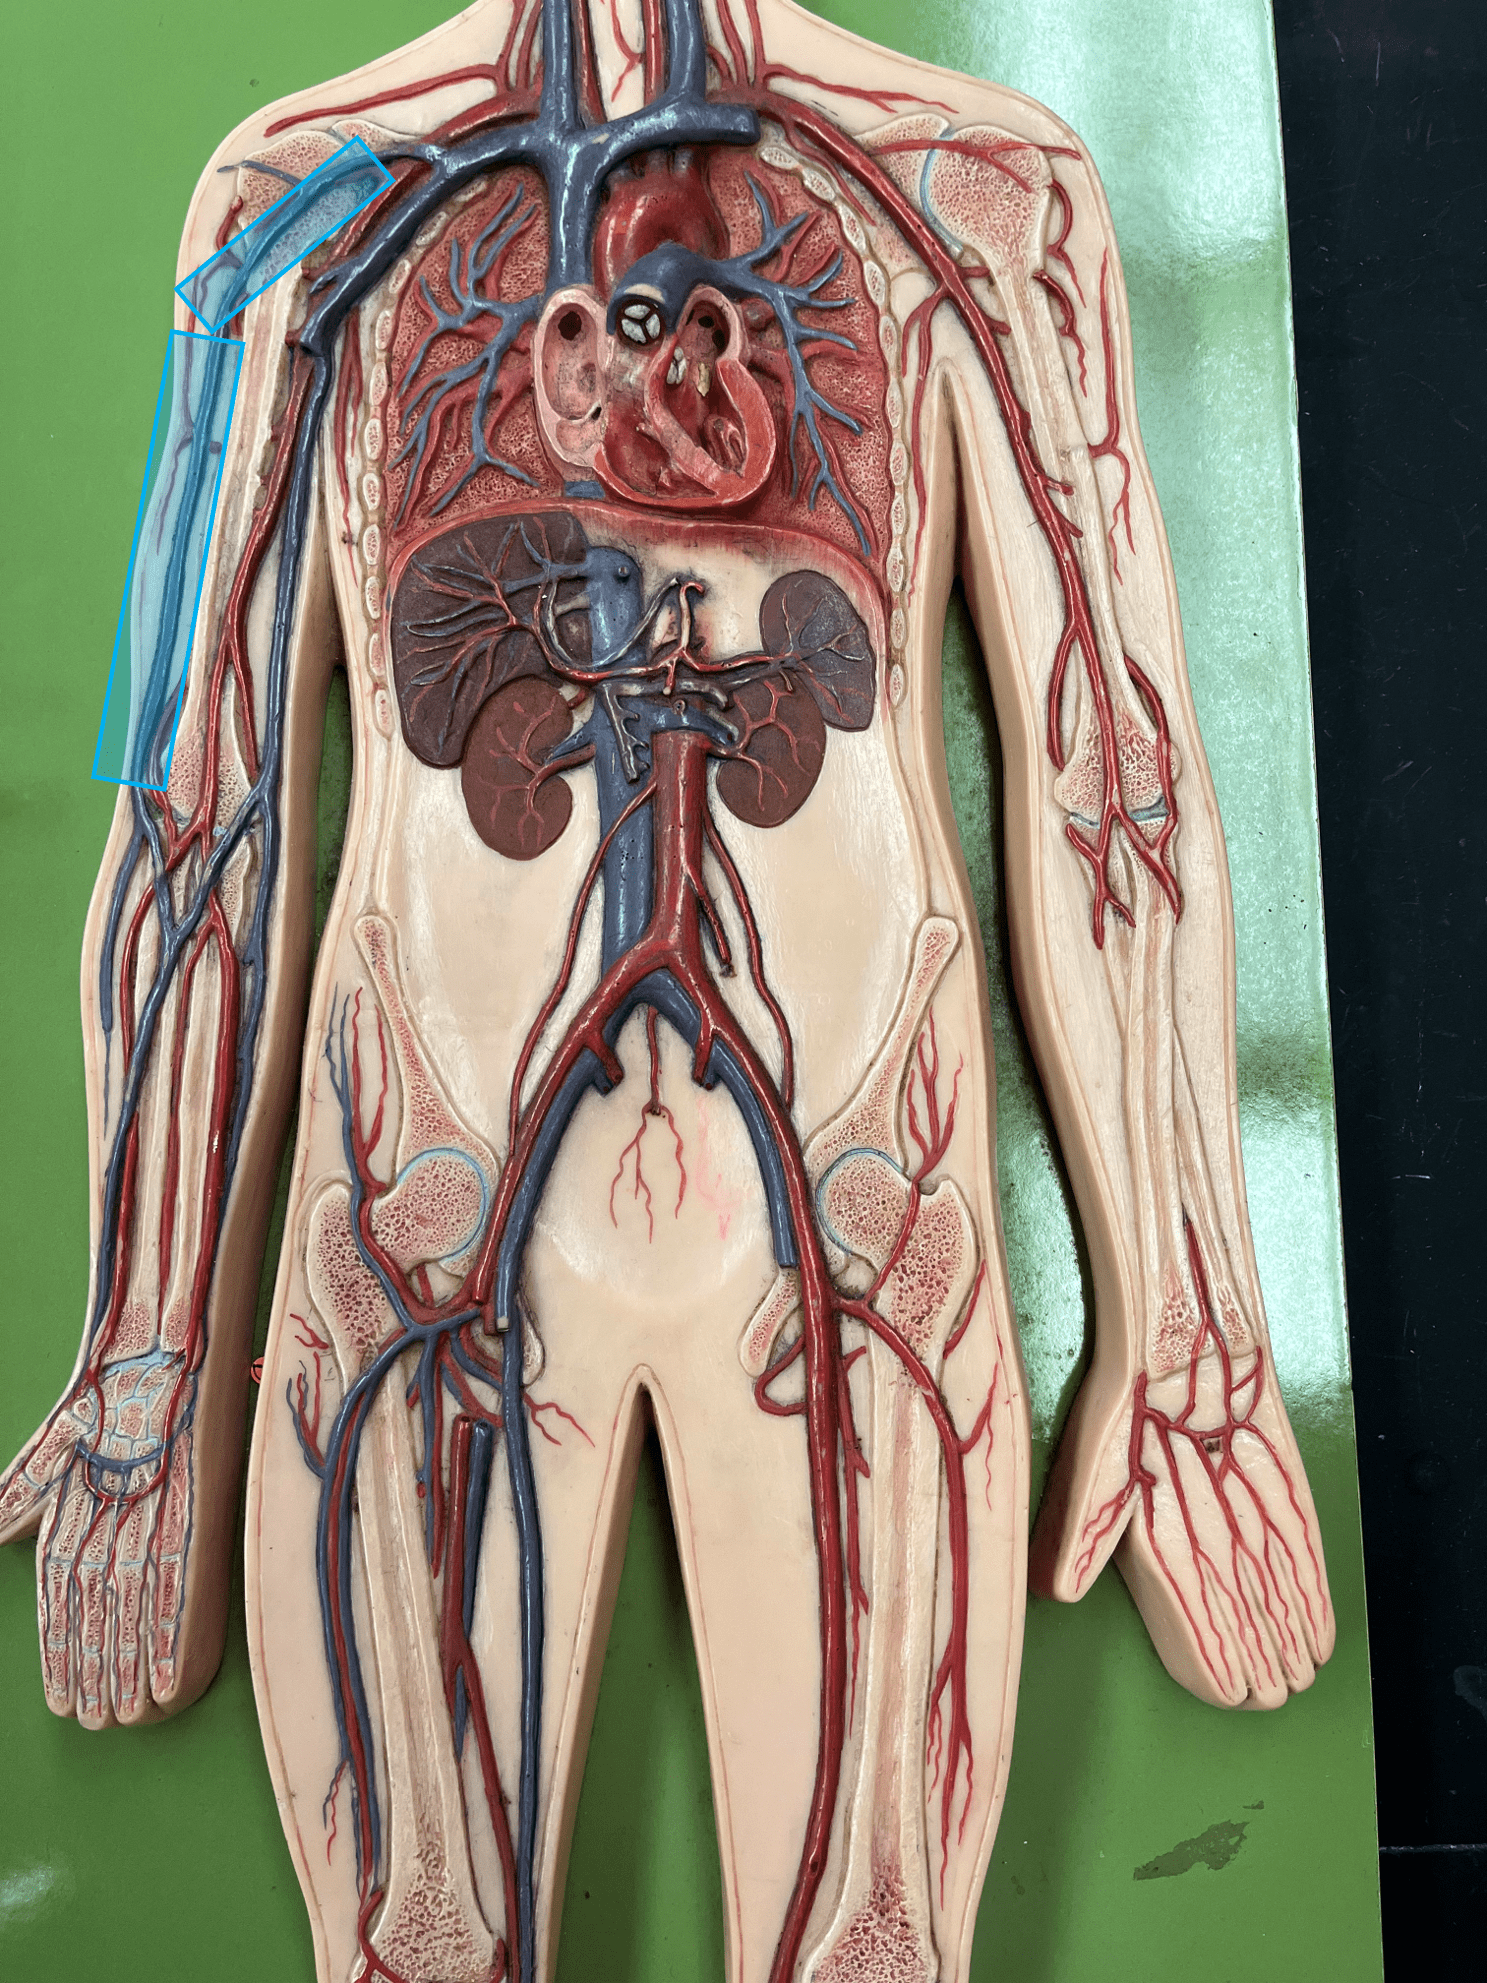

• Consists of an inner endothelium and an outer basement membrane.

• Also known as the tunica intima.

axillary vein